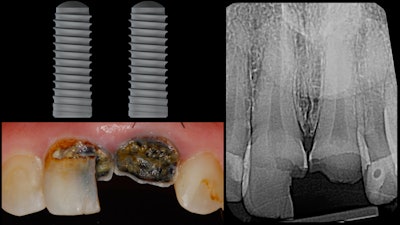

This patient presented with severe coronal caries for teeth #8 and #9. Anticipating both teeth to be nonrestorable, a treatment plan for two implants was developed (figure 1). Before treatment, the patient's intraoral condition was imaged using the Cerec Omnicam (Dentsply Sirona). A CBCT image was obtained using the Orthophos XG 3D.